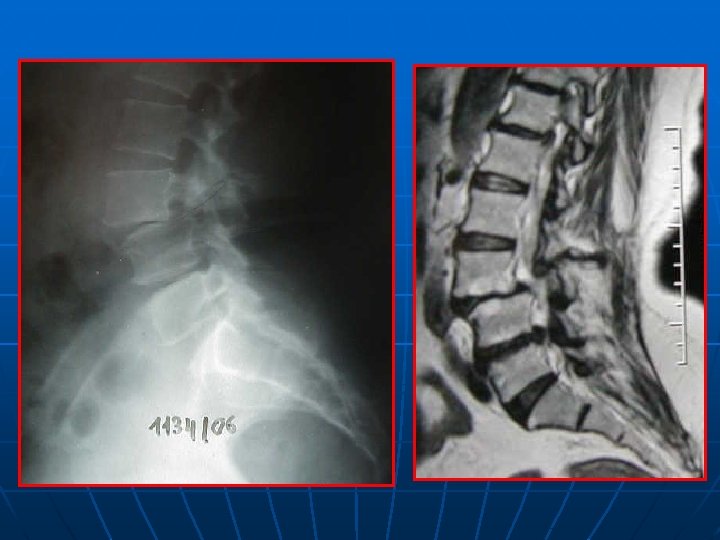

SPONDYLOLESTHESIS ISTHMIQUE Rx standard: face+profil+3/4 D-G Découverte au stade de déplacement n Lombalgies isolées: pas d’autres explorations n Lombosciatiques: Rx dynamiques+ grand format+IRM ( TDM peu d’apport) n

CONCLUSION n n LOMBALGIES ISOLEE: Rx standard RADICULALGIES: Rx dynamiques, grand format, IRM: étude du disque sus jacent pour l’étendue de l’arthrodèse